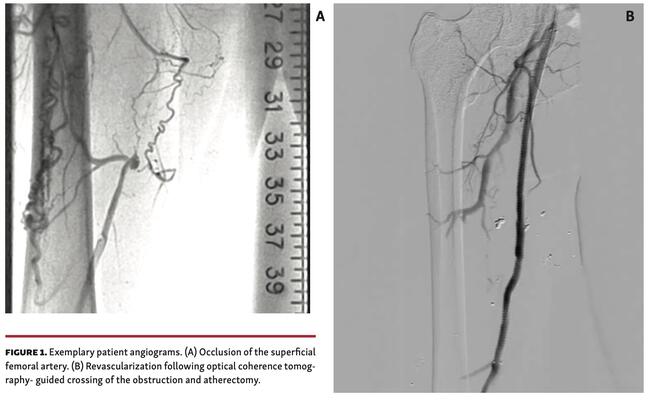

The pilot phase of the HIPACT study was a prospective assessment of histologic samples obtained from patients who underwent atherectomy of obstructive lesions in FP arteries. Patients were eligible for the study if they had chronic PAD (Rutherford-Becker categories 2–5) and occlusions within a FP segment (Figure 1). Patients were ineligible if they were taking oral anticoagulants, had a history of contrast allergy, or had undergone attempted treatment or atherectomy of the target CTO previously. Patients returned to the clinic within 6 months after the procedure for symptom assessment, ankle-brachial index evaluation, and documentation of any repeat procedures since treatment.

The patients were prepared for surgery following standard procedures. The target lesion was identified by angiography and its length was documented. With the lesion identified, the occlusion was traversed with an Ocelot crossing catheter (Avinger) (Figure 2) and then subsequently treated with TurboHawk directional atherectomy (Medtronic). Excised tissue was captured in the nosecone of the atherectomy device and collected at the end of the procedure, fixed in 10% neutral buffered formalin following standard methodology, and sent to the pathology lab.

A total of 19 patients participated in this pilot phase of the HIPACT study; they were predominantly male (67%) with a mean age of 72 ± 11.6 years. The CTO lesions were primarily (67%) in the superficial femoral artery (SFA), with 4 in a popliteal artery, and 1 each in the tibial peroneal trunk and the common iliac artery. All obstructions were crossed successfully by the crossing catheter with no dissections or perforations. Directional atherectomy reduced the obstructions such that blood flow was restored through the area of the obstruction, as determined by angiography. The amount of fluoroscopy time varied with the device used, with less than a minute of time (14 seconds) needed when the OCT-guided catheter was advanced through the obstruction to prepare a path for the atherectomy device (Figure 3).